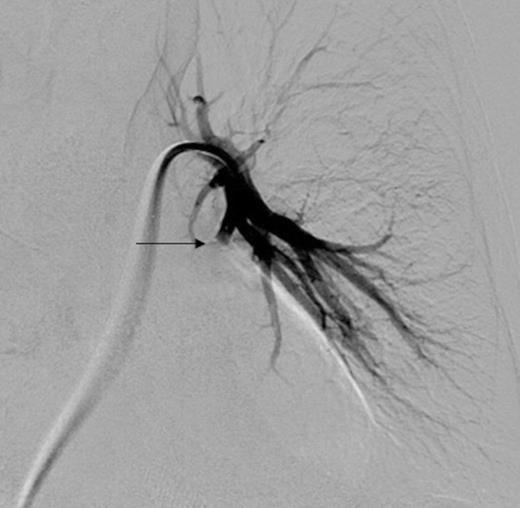

Left pulmonary artery digital subtraction angiography image demonstrating filling of left lower lobe aneurysm (arrow)

Digital subtraction angiography post deployment of the AVP 4 device in the PA branch feeding the aneurysm (arrow). No residual or collateral filling seen